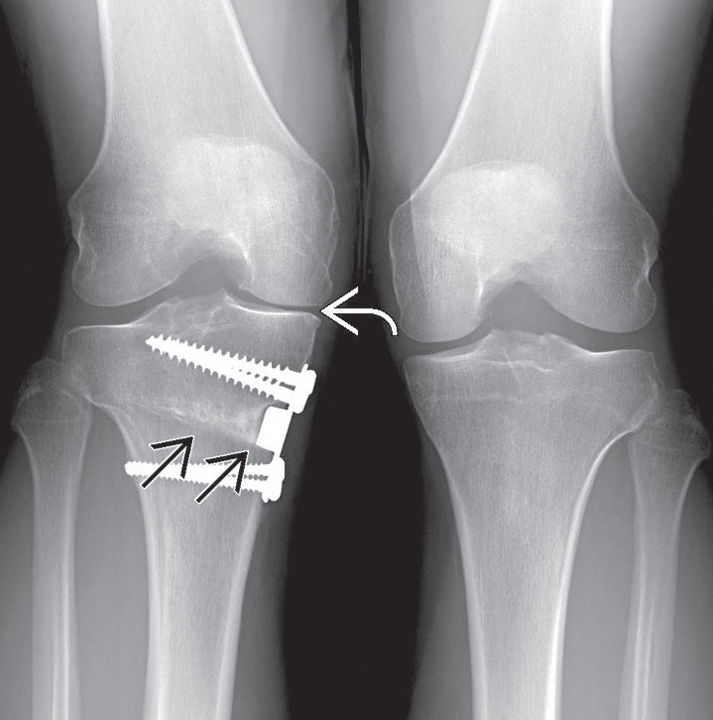

Kemik Düzeltici Ameliyatlar: Amaç, eklemin aşınmış bölgesine binen aşırı yükü ortadan kaldırıp, yükü sağlam tarafa aktarmaktır. Bunun için kemik kesilerek düzeltilir ve uygun açıya getirilerek tespit edilir. Genç hastalarda protez için zaman kazanmak amacıyla tercih edilir.

|

Sağ dizine kemik düzeltme ameliyatı yapılmış hastanın röntgen filmi